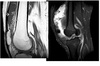

synovial sarcoma

Triple sign

Heterogeneous signal (combination of low, intermediate, and high) T2 signal from:

Solid mass

haemorrhage + necrosis

calcification (1/3).

Bowl of grapes sign = multiloculated appearance of mass with internal septa

Heterogenous enhancement of the solid components.

little to no perilesional oedema

Classic history -

paediatric patient with a multi-cystic appearing mass with well-defined margins around the knee joint

NOT in joint ie DOESNT arise from the synovium. Close to joint